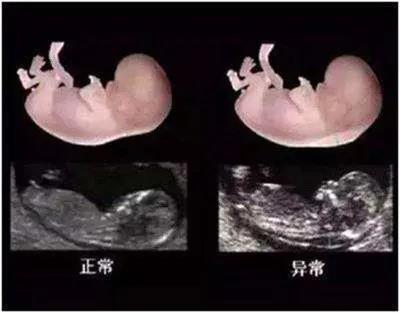

孕早期唐氏筛查是结合胎儿颈后透明带(NT)筛查的B超检查和血清生化检查结果对孕妈妈怀上染色体遗传疾病的胎儿进行风险评估。

早期唐氏筛查能检测出相当高比例的唐氏综合症和其他染色体异常病例。